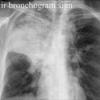

Air bronchogram

Date: 04/29/2014

Views: 9942